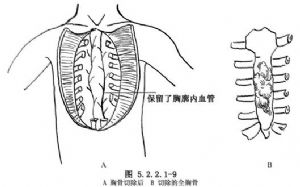

胸骨腫瘤應完全或部分切除胸骨,應遊離未受累的胸肌至肋軟骨與肋骨交界處。胸骨完全切除時,須顯露上至胸鎖關節,下達肋弓(圖5.2.2.1-8)。避免損傷胸膜(圖5.2.2.1-9A、B)。